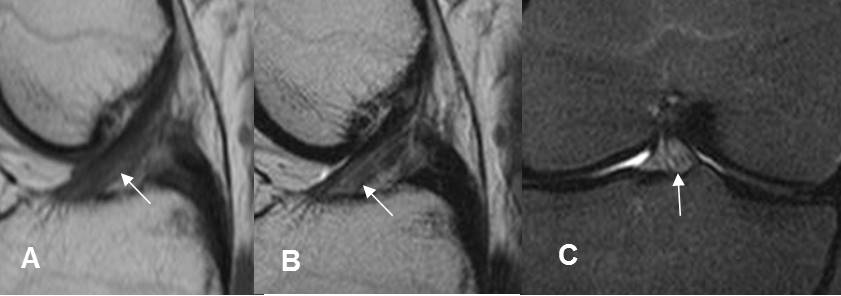

Fig 164. Esguince grado I.

A: RM sagital en T1, B: RM sagital en T2 y C: RM coronal en STIR. Alteración de la señal en el tercio distal del LCA, pero sin ruptura de fibras, por esguince GI.